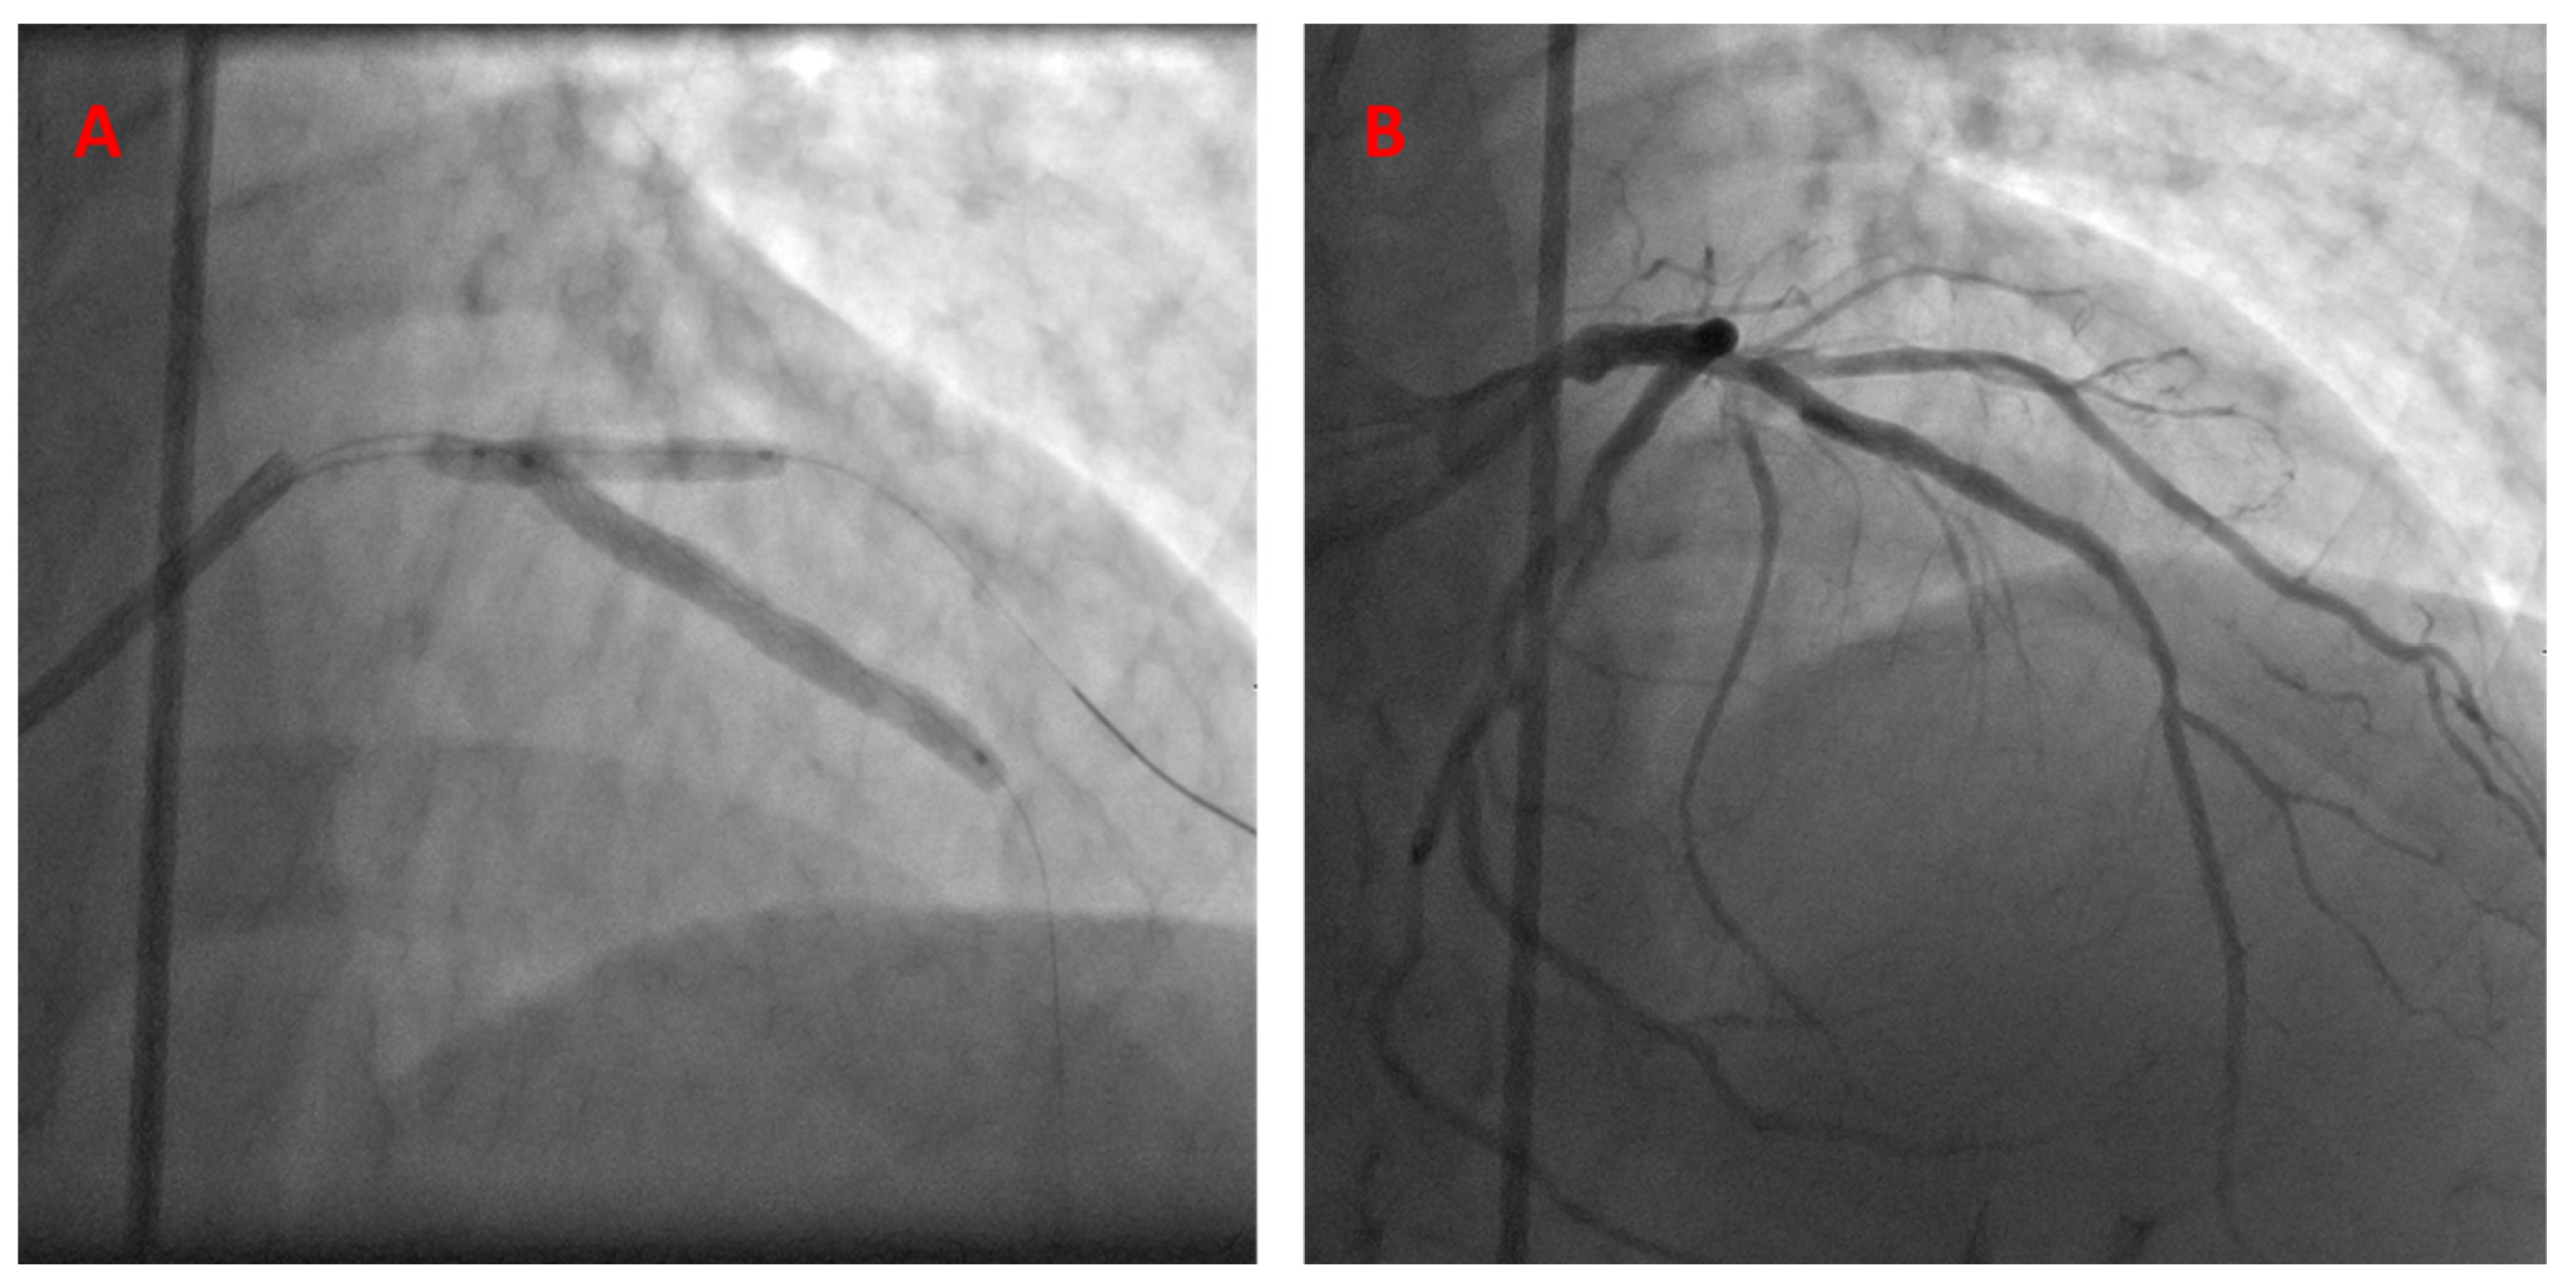

PCI description: The operator chose a 7 Fr guide catheter for his approach in this case. After engaging the left main coronary artery, 2 wires were advanced antegrade into the LAD and diagonal artery. The LAD lesion was pre-dilated using a 2.75 semi-compliant balloon. A resolute integrity 3.0 × 38 stent was then advanced and positioned in the LAD, starting at the exact takeoff point of the diagonal artery. A semi-compliant 2.75 balloon was then advanced and positioned into the diagonal artery, with the proximal part slightly extending into the LAD. The stent was deployed first, followed by balloon inflation. Angiographic stenosis severity in the LAD was reduced from 70% down to 0%, with a TIMI-3 flow recorded pre- and post-operation. The diagonal artery had mild 30% disease, with a TIMI-3 flow that did not change after intervention (Figure 3, Video S2).

Figure 3.

The kissing BS technique, utilized to treat LAD-D1 bifurcation disease (A). Post-stent deployment—final angiographic results (B).